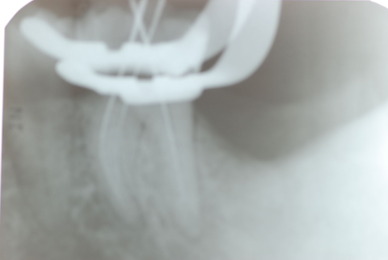

これぞ医師の姿ではないでしょうか。![11229551_834920046584649_8659418848563116234_n[1]](https://livedoor.blogimg.jp/netdental/imgs/c/0/c098deb4.jpg)

![11053897_834920076584646_6691737990508884178_n[1]](https://livedoor.blogimg.jp/netdental/imgs/b/b/bb679b8f.jpg)

![11010956_834920133251307_8897824032330972564_n[1]](https://livedoor.blogimg.jp/netdental/imgs/c/2/c2aa3129.jpg)

![10403096_834920093251311_4823181277198290695_n[1]](https://livedoor.blogimg.jp/netdental/imgs/b/7/b77edc79.jpg)